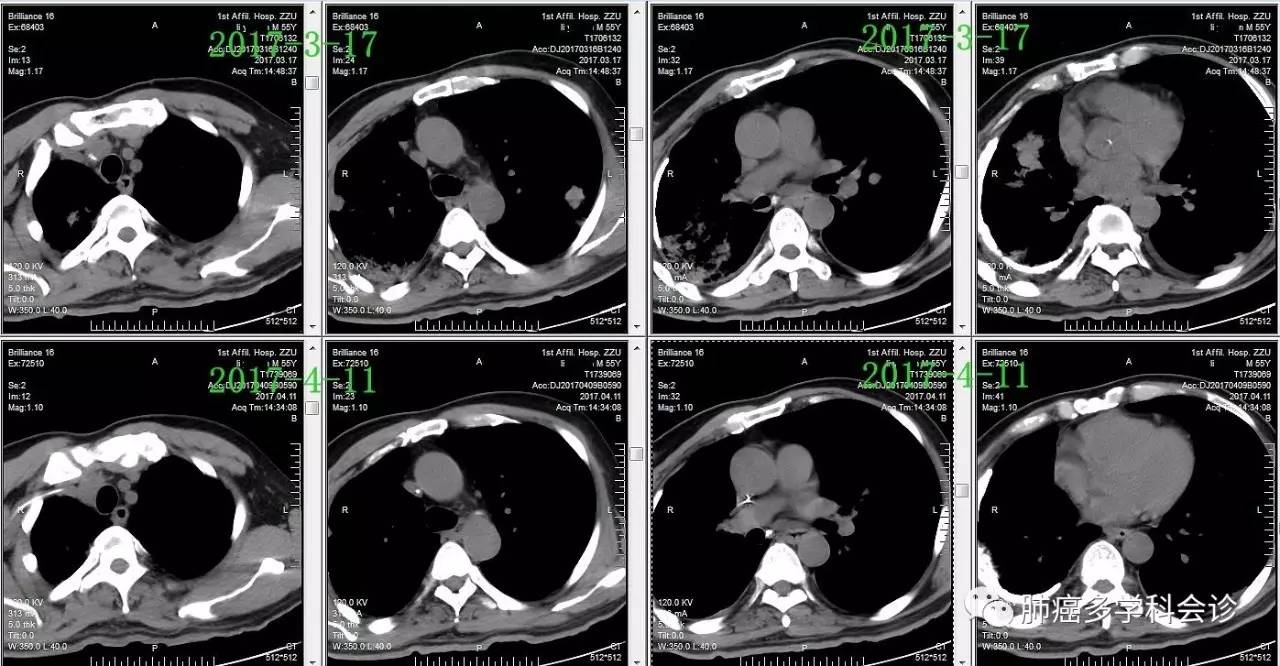

以下化疗前1周(2017-3-17)和第一周期化疗结束后(2017-4-11)两肺转移灶和右胸膜腔病灶的变化: